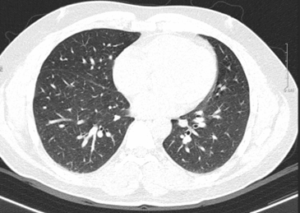

CA LÂM SÀNG: Điều trị ung thư phổi không tế bào nhỏ di căn, giai đoạn muộn tại Trung tâm Y học hạt nhân và Ung bướu-Bệnh viên Bạch Mai

CA LÂM SÀNG: Điều trị ung thư phổi không tế bào nhỏ di căn, giai đoạn muộn tại Trung tâm Y học hạt nhân và Ung bướu-Bệnh viên Bạch Mai GS. TS. Mai Trọng Khoa, PGS. TS. Phạm Cẩm Phương, PGS. TS. Phạm Văn Thái ThS. Lê Quang Hiển, BSNT....